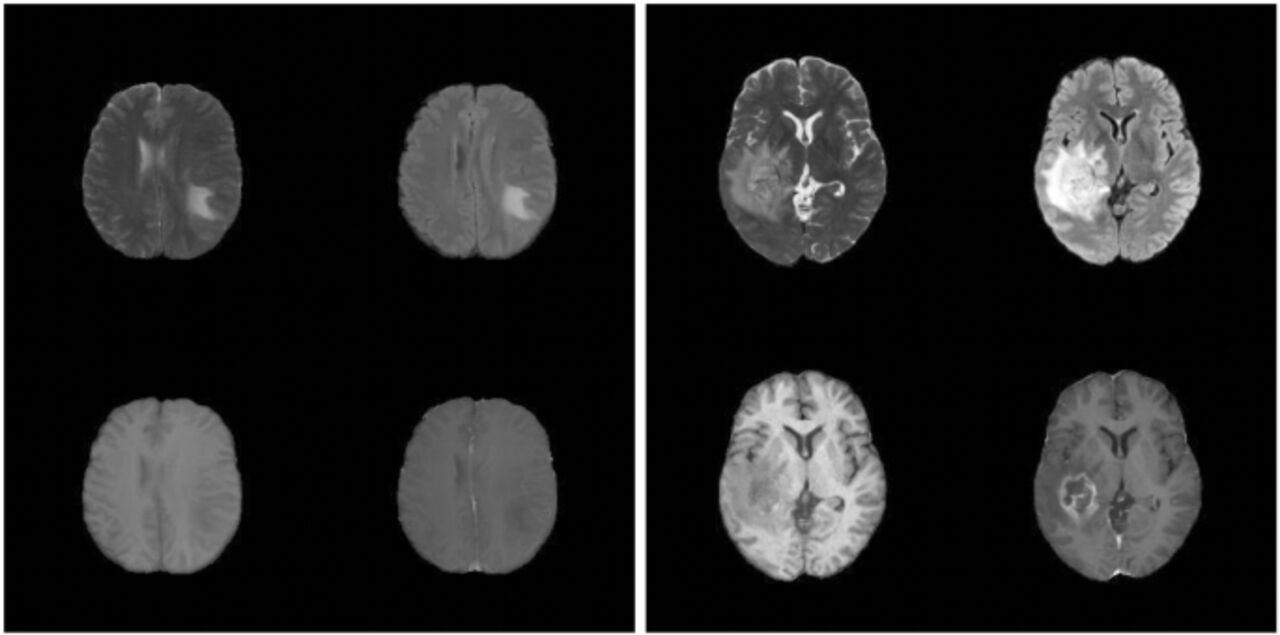

Bilden bestär av två delar: Fyra snittbilder av en hjärna på ena sidan och fyra snittbilder av en annan hjärna på andra sidan

En av dessa två bilder är riktig och en är syntetisk. Vilken tror du är syntetisk?*

*Rätt svar på bildfrågan i översta bilden finns i figur 5 i forskningsartikeln på nature.com